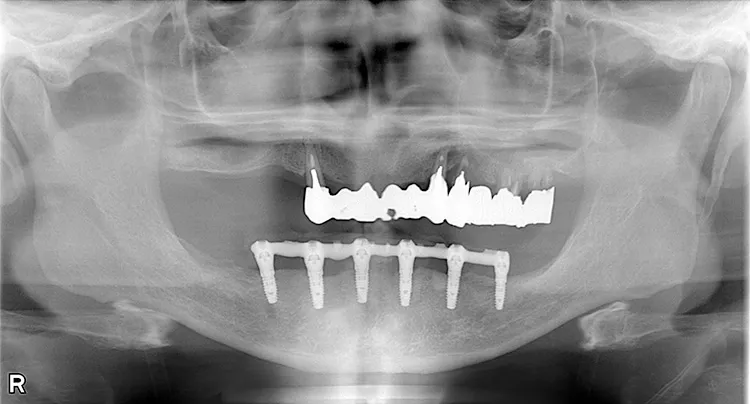

症例8/

下顎ボーンアンカードブリッジ

- 治療期間

- 6ヶ月

- 費用

- 265万円(税込)

治療前

治療後

レントゲン画像

治療内容

ボーンアンカードブリッジの下顎症例です。同じようにインプラント6本で上部構造を支えることができます。